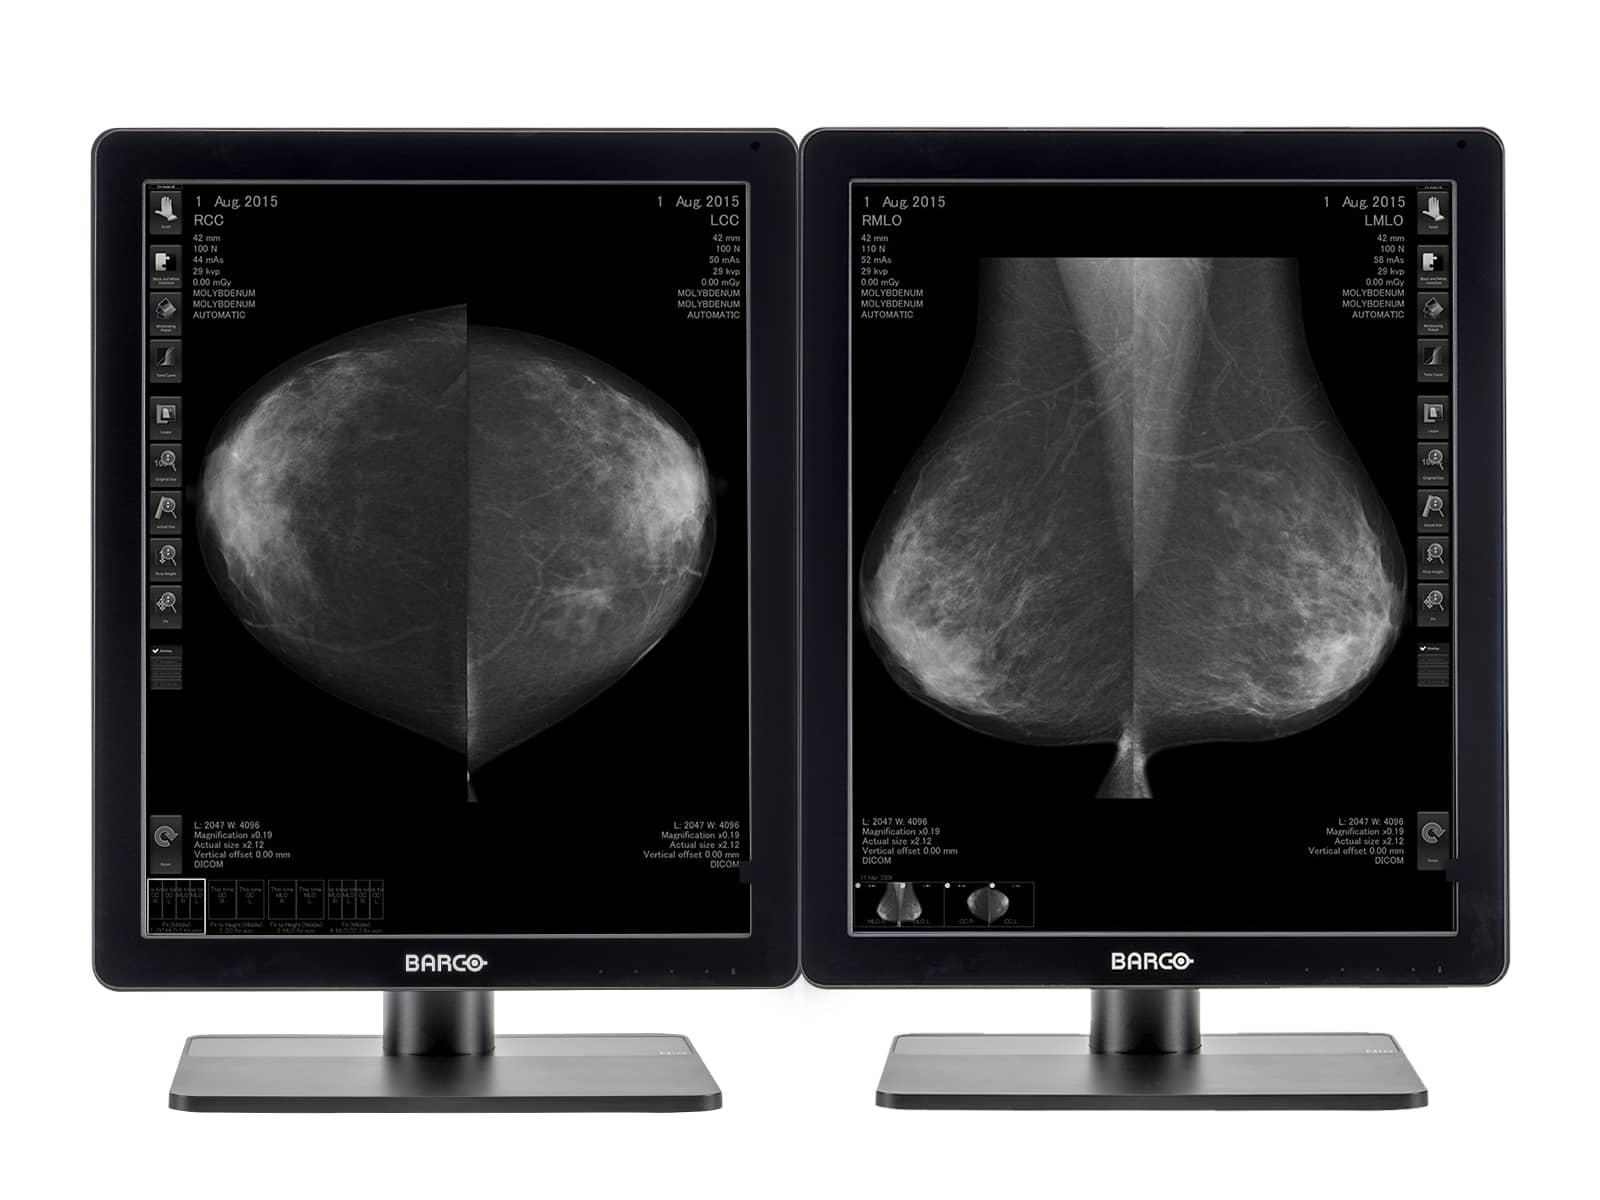

Barco Nio MDNC-6121 5MP 21" Color LED Mammo 3D-DBT Breast Imaging Display

Barco Nio MDNG-5221 5MP 21" Grayscale LED 3D-DBT Mammography Breast Imaging PACS Display

Barco Coronis MDMG-5221 5MP 21" Grayscale Tomosynthesis 3D-DBT Mammography Display